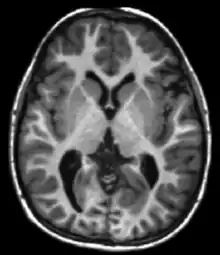

| Fluid-attenuated inversion recovery | FLAIR | Fluid suppression by setting an inversion time that nulls fluids | High signal in lacunar infarction, multiple sclerosis (MS) plaques, subarachnoid haemorrhage and meningitis (pictured).[15] | ![]() | |

Each tissue returns to its equilibrium state after excitation by the independent relaxation processes of T1 (spin-lattice; that is, magnetization in the same direction as the static magnetic field) and T2 (spin-spin; transverse to the static magnetic field). To create a T1-weighted image, magnetization is allowed to recover before measuring the MR signal by changing the repetition time (TR). This image weighting is useful for assessing the cerebral cortex, identifying fatty tissue, characterizing focal liver lesions, and in general, obtaining morphological information, as well as for post-contrast imaging. To create a T2-weighted image, magnetization is allowed to decay before measuring the MR signal by changing the echo time (TE). This image weighting is useful for detecting edema and inflammation, revealing white matter lesions, and assessing zonal anatomy in the prostate and uterus.